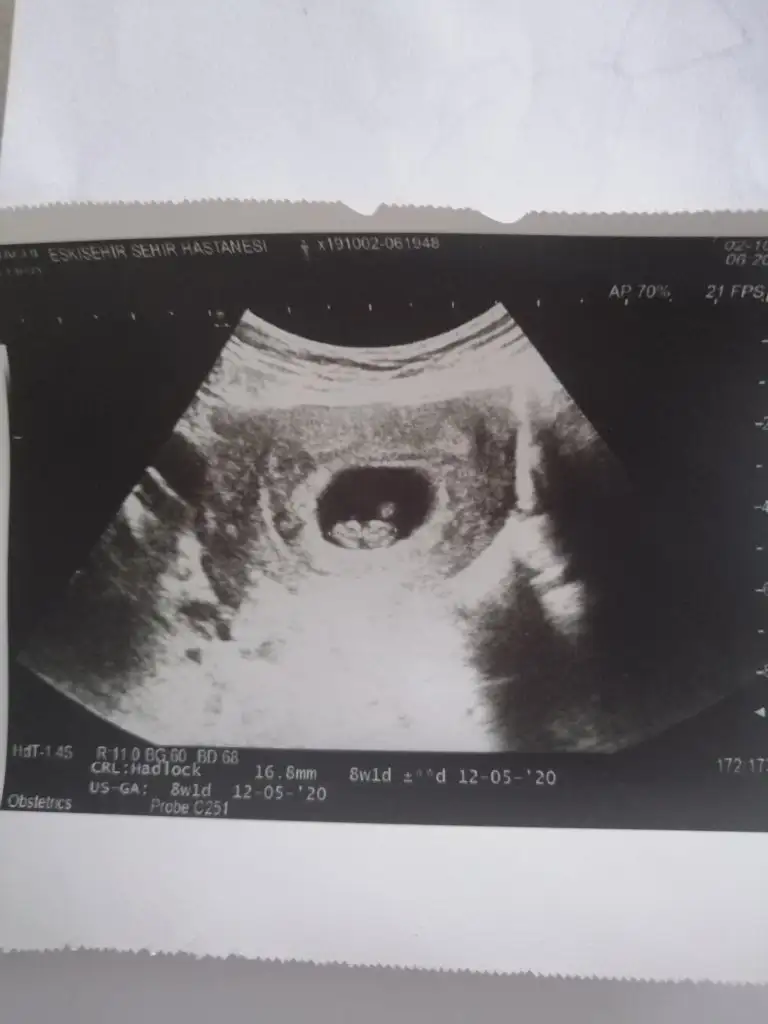

Banada erkek demiştiniz hatta baya net erkek demiştiniz kız diyince doktor şaşırmıştınız bnde çok şaşırmıştım tabi çünkü baya umutlanmıştım 2 kızım var doğal olarak değişik olsun istemiştim tabiki Rabbim in dediği olur ama hala erkek hissediyorum ayrıntılıda pozisyonu tersti cinsiyeti gözükmüyor demişti perinatolog ama 2 doktor kız gibi biride düşük kalitede bir cihazda kız demişti sonra rüyamda bebeğimin isminin koyulduğunu gördüm mavi nüfus kağıdında Ali arif yazıyordu bilemiyorum hala erkek hissediyorum pembe kıyafetleri almama rağmen

az kaldı sonucu görmeye herşey den önce Rabbim sağlıklı ve hayırlı evlatlar nasip etsin bizlere